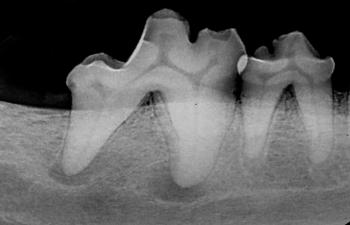

Most of the tooth is located below the gumline and out of view. Intraoral radiography can yield invaluable diagnostic information about your patients’ oral health.